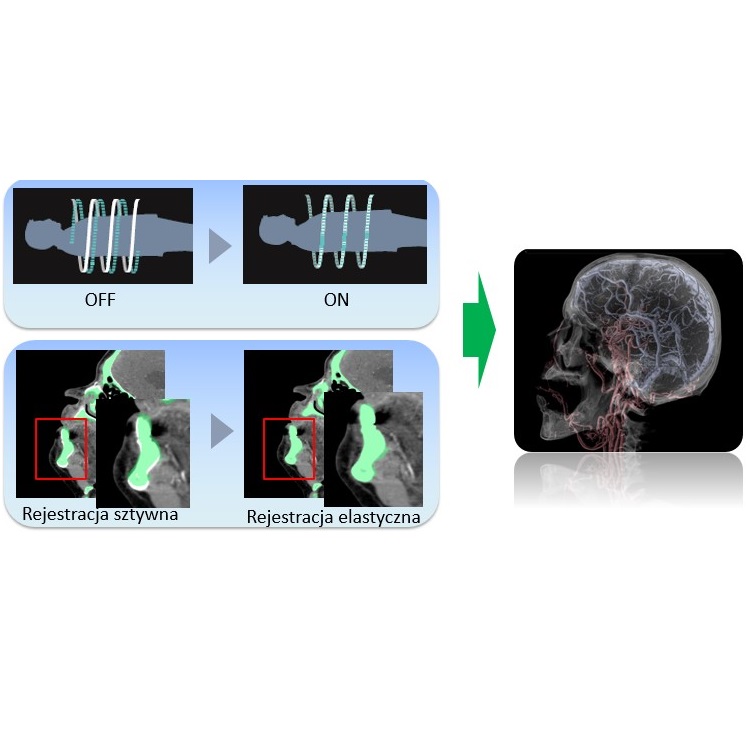

- SYNAPSE 3D - Wszystko co może być zrekonstruowane w 3D, rekonstruujemy - zaawansowana kliniczna analiza post-processingowa do wizualizacji badań z modalności CT i MR